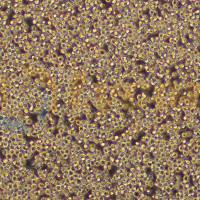

| 形态特征 | 上皮样 |

| 生长特性 | 贴壁 |

| 培养条件 | 气相:空气,100% 无二氧化碳培养 温度:37℃ |

| 传代方法 | 1:2传代 |

| 细胞简介 | SW1417是一种人结肠直肠腺癌细胞系,源自人结肠直肠腺癌组织,常用于癌症生物学研究、药物筛选及肿瘤发生机制探索。该细胞系保留腺癌特性,适用于体外模型构建、基因表达分析和化疗药物敏感性测试。 |